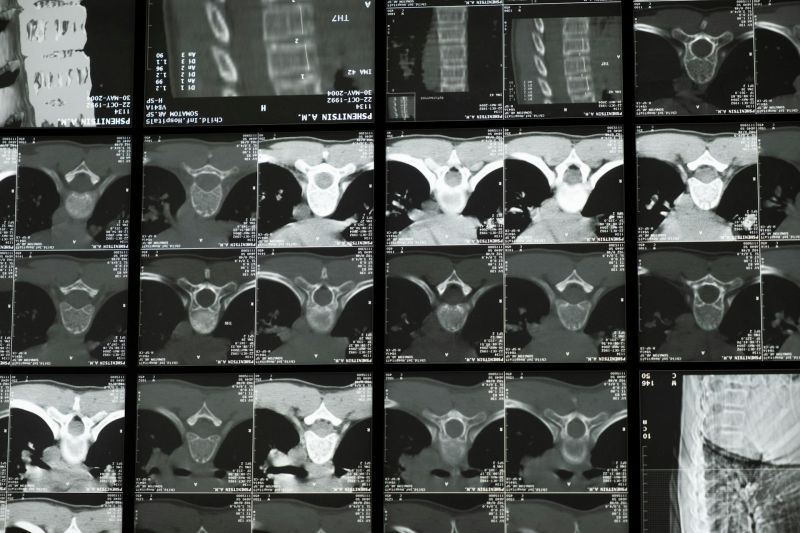

MSCT snimanje kičmeMSCT snimanje kičme

Balkan Medic pruža uslugu multislajsni CT skener kičme za precizno sagledavanje vratnog, grudnog, slabinskog i krstačnog dela kičmenog stuba.

Multislajsni CT skener kičme omogućava detaljno snimanje koštanih i okolnih struktura kičmenog stuba. Snimanje se obavlja pomoću rendgenskih zraka i savremene računalne obrade, čime se dobijaju jasni preseci u tankim slojevima. Ovakav pregled pomaže u preciznom sagledavanju promena koje mogu biti uzrok bola, ograničene pokretljivosti ili neuroloških tegoba.